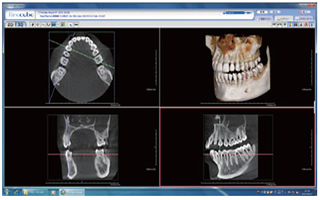

新たにアーム型X線CT診断装置を導入致しました。

3次元CTレントゲンの導入

当院では、より正確で精密な治療を行うために、新たに3次元CTレントゲンを導入いたしました。①3次元CTレントゲンとは?

従来のレントゲン写真は2次元(平面)での撮影です。それに対して、当歯科医院で導入した3次元CTレントゲン写真であれば、立体的な撮影が可能になりました。これにより、口腔内の骨の構造を詳しく理解でき、より正確で精密な治療が実現できるようになりました。安全性

レントゲン撮影と耳にされると「被曝はしないの?」と疑問に思われる方がいらっしゃるかと思います。しかし、歯科用のCTは医科用のCT(胸部等)と比較して被曝量は少なく危険性は少ないと言われております。②3次元CTレントゲンを利用した治療

インプラント治療における利用

一般歯科治療にも利用

歯周病治療や親知らずの治療を行う際にも利用します。